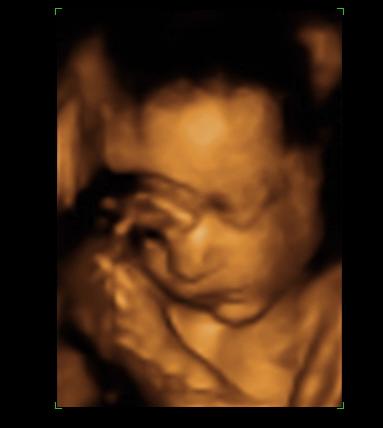

Megjöttünk az Istenhegyiről.

Az eredmények:

down 1:5272

edwards 1:82779

patau: 1:194866

a szűrés eredménye:NEGATÍV :D :D :D :D :D :D :D :D :D :D :D :D

a biometriai adatok alapján a grv.s.: 12hét+5nap

szerdán megyek a saját dokimhoz

később még hozok képeket

Mondjuk szegény babica aludt, nem is akarózott neki felébredni, úgyhogy a doki megküzdött, mire le tudta mérni. Pont nem jól feküdt, és az istennek sem akart megfordulni. :lol: Lusta a kicsike. A szívhangja szép, szabályos.